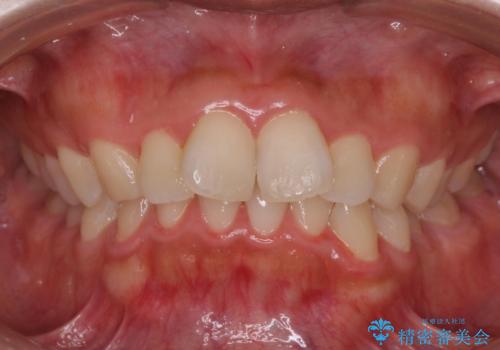

- 前歯のがたつきを主訴に来院。

右下の犬歯が歯ぐきが痩せて、歯肉退縮しておりそれを抜歯しました。

上の前歯はIPRを行なっています。

右下の犬歯の1本抜歯で最小限の抜歯で並べることができました。

奥歯も上下交互になるようにかみ合わせることができました。